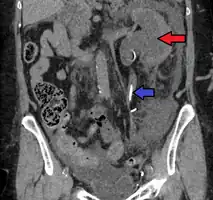

Hydronephrosis due to a kidney stone at the ureteral vesicular junction seen on CT scan

The choice of imaging depends on the clinical presentation (history, symptoms and examination findings). In the case of renal colic (one sided loin pain usually accompanied by a trace of blood in the urine) the initial investigation is usually a spiral or helical CT scan. This has the advantage of showing whether there is any obstruction of flow of urine causing hydronephrosis as well as demonstrating the function of the other kidney. Many stones are not visible on plain X-ray or IVU but 99% of stones are visible on CT and therefore CT is becoming a common choice of initial investigation. CT is not used however, when there is a reason to avoid radiation exposure, e.g. in pregnancy.